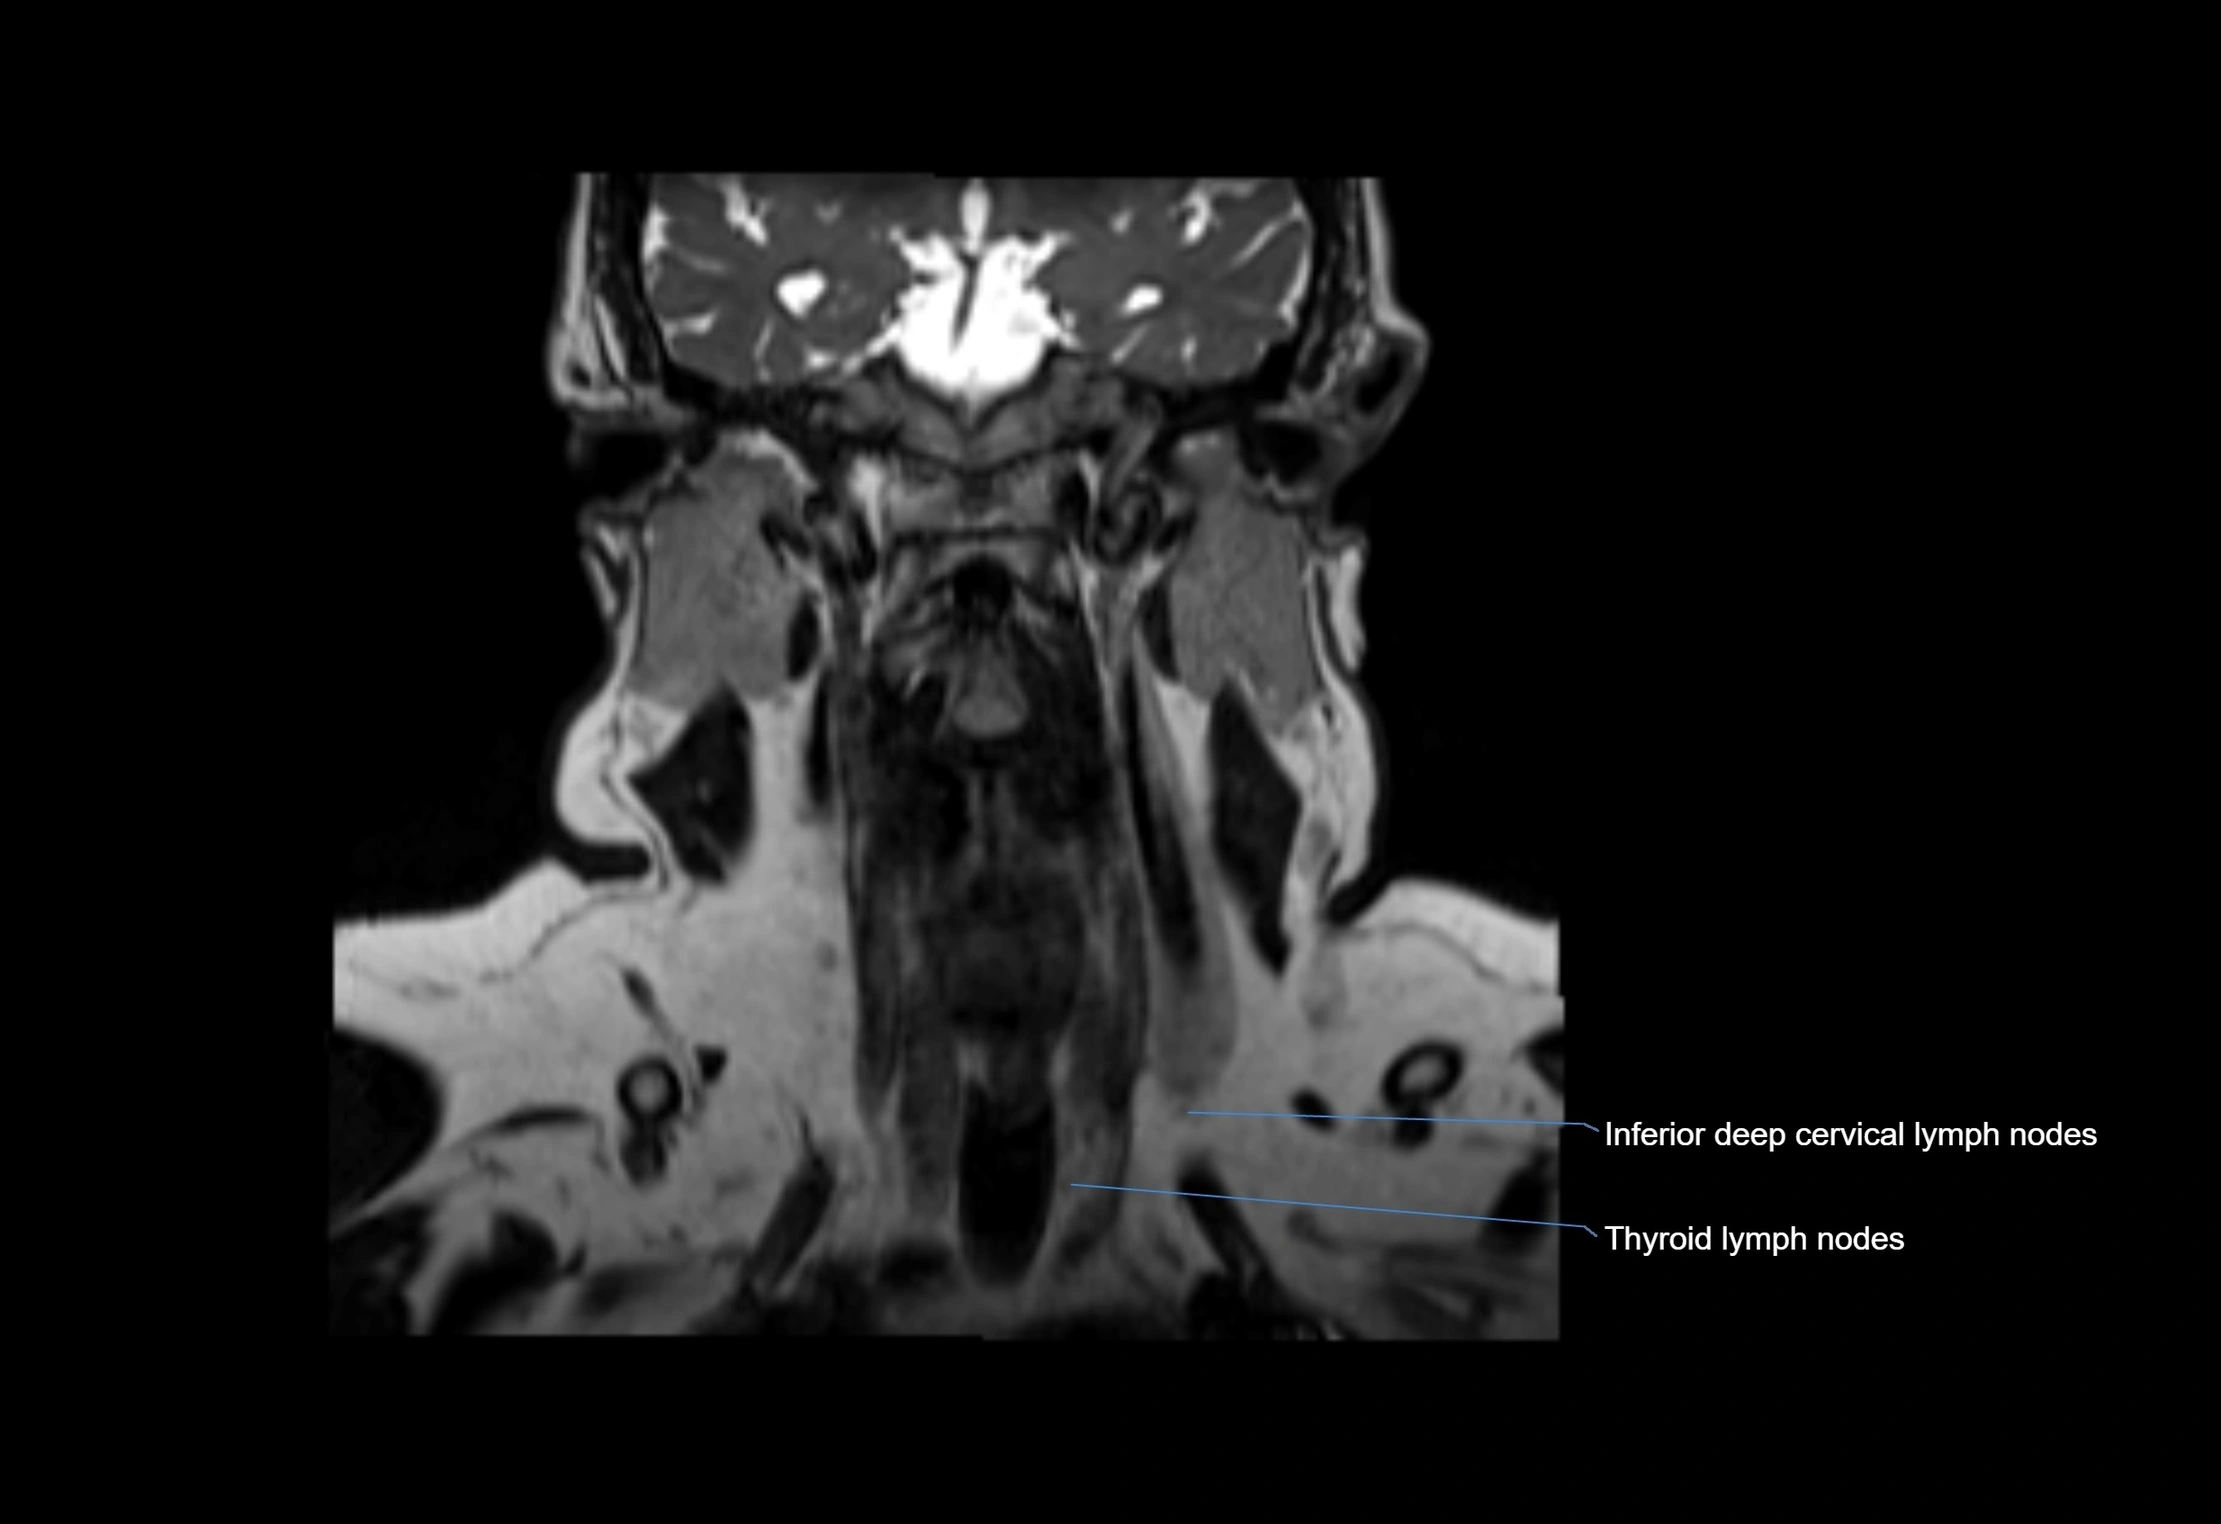

MRI Appearance

T1-weighted images:

• Normal accessory nodes appear as small, oval hypointense to intermediate signal structures within subcutaneous fat

• Surrounded by hyperintense fat, enhancing contrast for visualization

• Pathological nodes may appear enlarged or rounded, sometimes with cortical thickening

T2-weighted images:

• Nodes show intermediate signal, with surrounding fat bright

• Useful for detecting edema, inflammation, or infiltration

• Fatty hilum may appear slightly hyperintense relative to cortex

MRI images

image